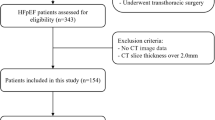

Study Population

Between January 2019 and June 2022, a retrospective cohort study including 107 consecutive patients who underwent CCTA followed by invasive coronary angiography (ICA) within 3 months at The Second Affiliated Hospital, Zhejiang University School of Medicine, Hangzhou, Zhejiang, China, was performed. A total of 129 healthy controls were also included in the study to compare the CCTA-derived parameters of the patients with those in the normal population. A flowchart of this study is illustrated in Fig. 1.

All participants were of Asian ethnicity. The inclusion criteria were as follows: (1) heart failure defined according to the European Society of Cardiology (ESC) guidelines [2]; (2) New York Heart Association [NYHA] class II-IV or signs consistent with the Framingham criteria; (3) no coronary artery stenosis on coronary angiography; and. (4) CT-FFR > 0.8. The exclusion criteria included (1) missing images or poor image quality; (2) incomplete laboratory tests; and (3)) incomplete ultrasound data and loss to follow-up. All patient information, including demographic characteristics, medical history, laboratory tests, and echocardiography results, was collected after admission.